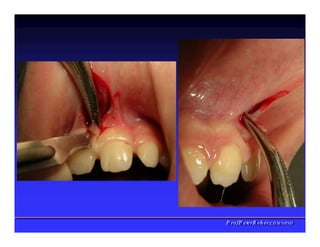

Face interna dos Lábios

✓Freios Labial

superior

✓Freio Labial

inferios

✓Bridas

Musculares